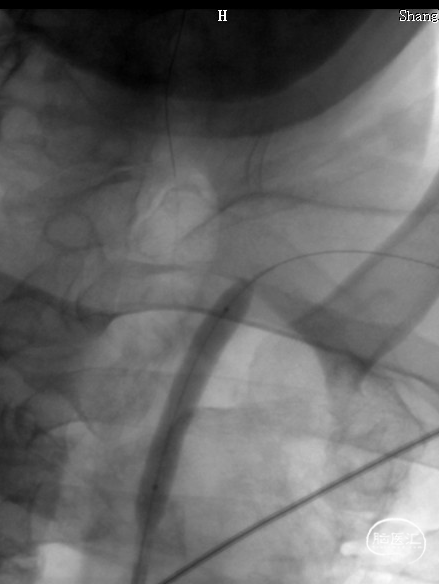

DSA:LSub。

DSA:L-CCA。

0.018*300cm 外周导丝至左肱动脉,0.014*200cm 通桥北斗SS™神经血管导丝超选至左椎V2段远端。

沿0.018*300cm 外周导丝送入6*40 外周球囊送至左侧锁骨下动脉狭窄处,压力泵逐渐加压到6atm。

撤出球囊后见残余狭窄40%。

再次沿0.018*300cm 外周导丝送入6*40 外周球囊达LSub狭窄部位,压力泵逐渐加压到8atm,见残余狭窄20%。